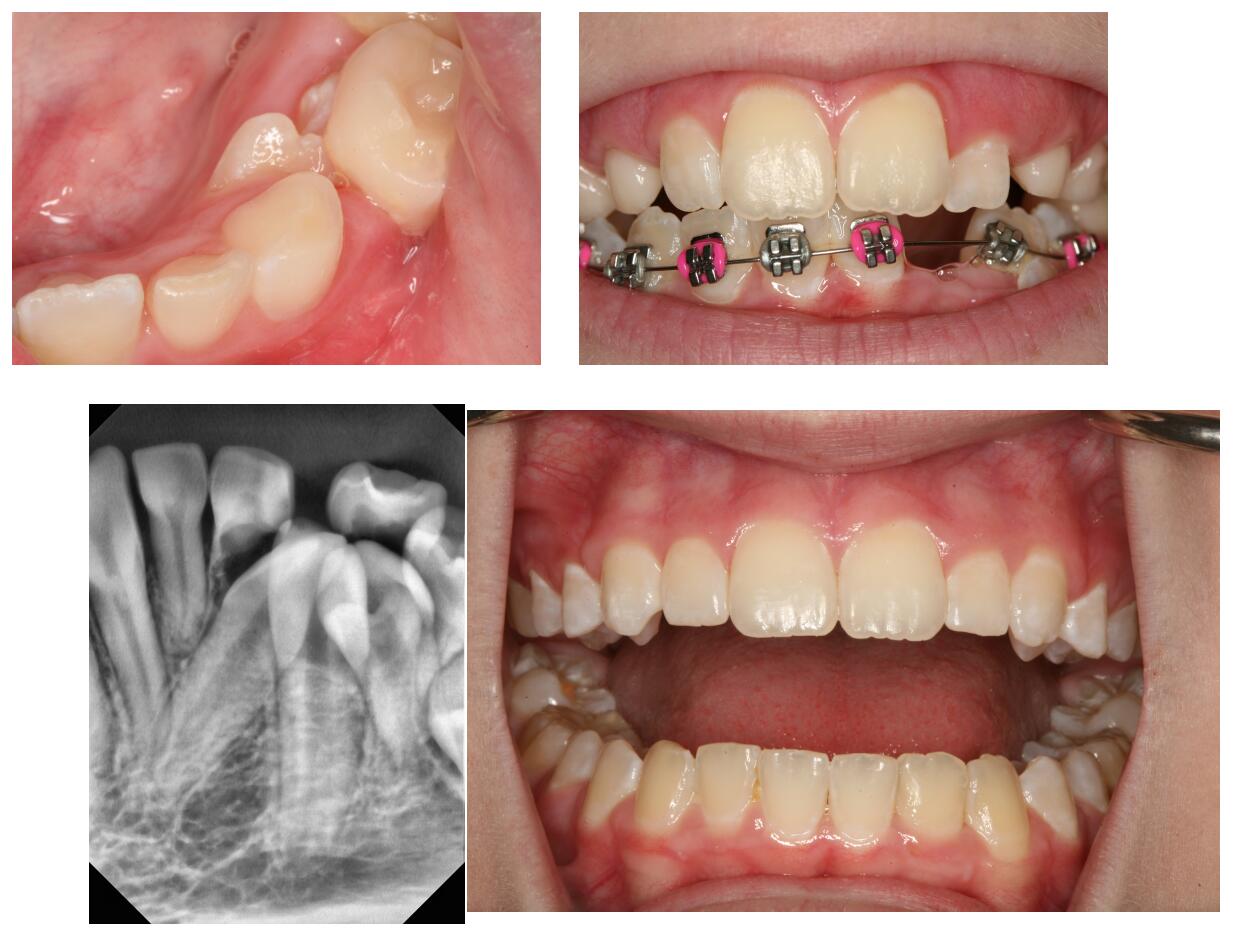

Assisted Eruption of Impacted Teeth at Warren Orthodontics, Springville Do Orthodontists Deal With Tmj When considering the question of whether there is a relationship between orthodontic treatment and tmj. Orthodontic appliances can help alleviate tmj. Orthodontic treatment for tmj/tmd can come in various forms. The january 2022 issue marks 30 years since the american journal of orthodontics and dentofacial orthopedics (ajodo) published a special. The correct functioning of the temporomandibular joint (tmj) is of. Do Orthodontists Deal With Tmj.